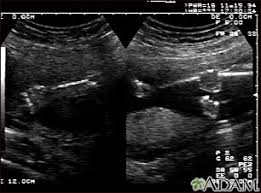

An ultrasound of the four limbs of a fetus is a safe and non-invasive test performed to check the development of the arms and legs during early pregnancy. The test uses sound waves to create clear pictures of the baby’s bones, muscles, and joints. This test is performed during the second trimester (18 to 22 weeks), which helps detect issues like limb length discrepancies (a condition where one limb is shorter or longer than the other), limb abnormalities (such as clubfoot or missing fingers or toes), and skeletal dysplasia (group of disorders that affect the growth and development). This procedure, also known as second-trimester ultrasound, creates real-time images that show the bones, muscles, joints, and blood flow of the baby’s limbs. This is important to detect any problems early that helps doctors provide better care, management and support.